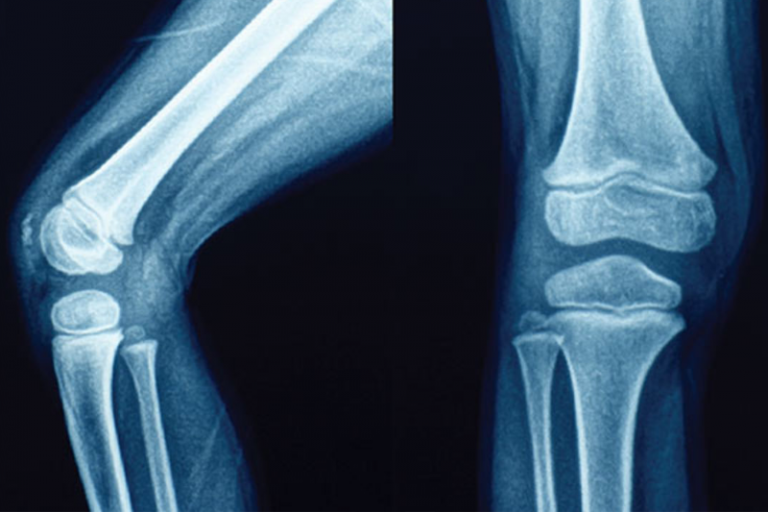

最近一些研究有了答案。主要是當關節初「動」時,肌腱的作用力(如拉力等)會瞬間先使關節產生形變,最多可增大至7%,形變產生關節腔負壓。這負壓雖微,但足以使關節囊凹陷(被吸入),使溶於滑液內的氮氣、氧氣、二氧化碳等氣體,部分氣化成氣泡。累積在人體的關節之間,降低關節的潤滑度,使關節變得較僵硬,當我們折指頭、做體操或其他大動作時,關節內的相對活動加大,把氣泡擠破便會發出聲音(當然,有時伴隨著關節內骨骼相互磨擦的聲響),關節也會有較舒服、開展的感覺;但是氣泡被擠破,其實仍然存在關節內,因此過一段時間,又會聚積在一起,又可以發出聲音。